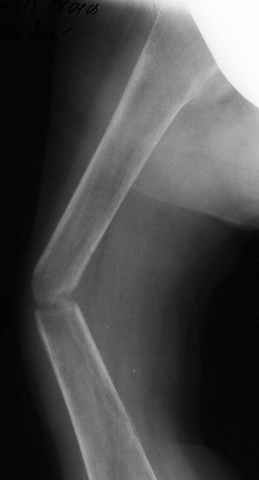

A male 23 y.o. many years sustained severe osteoporosis with multiple fractres of long bones and ribs. Last 4 years was not able to leave chair. Some x-rays attached. What may cause the situation? Juvenile osteoporosis should have been recovered spontaneously to date. What lab research is needed? What is most likely diagnosis? Can such fractures be treated more aggressively? What medications can improve bone quality? Biphosphonates? Somatotropin?